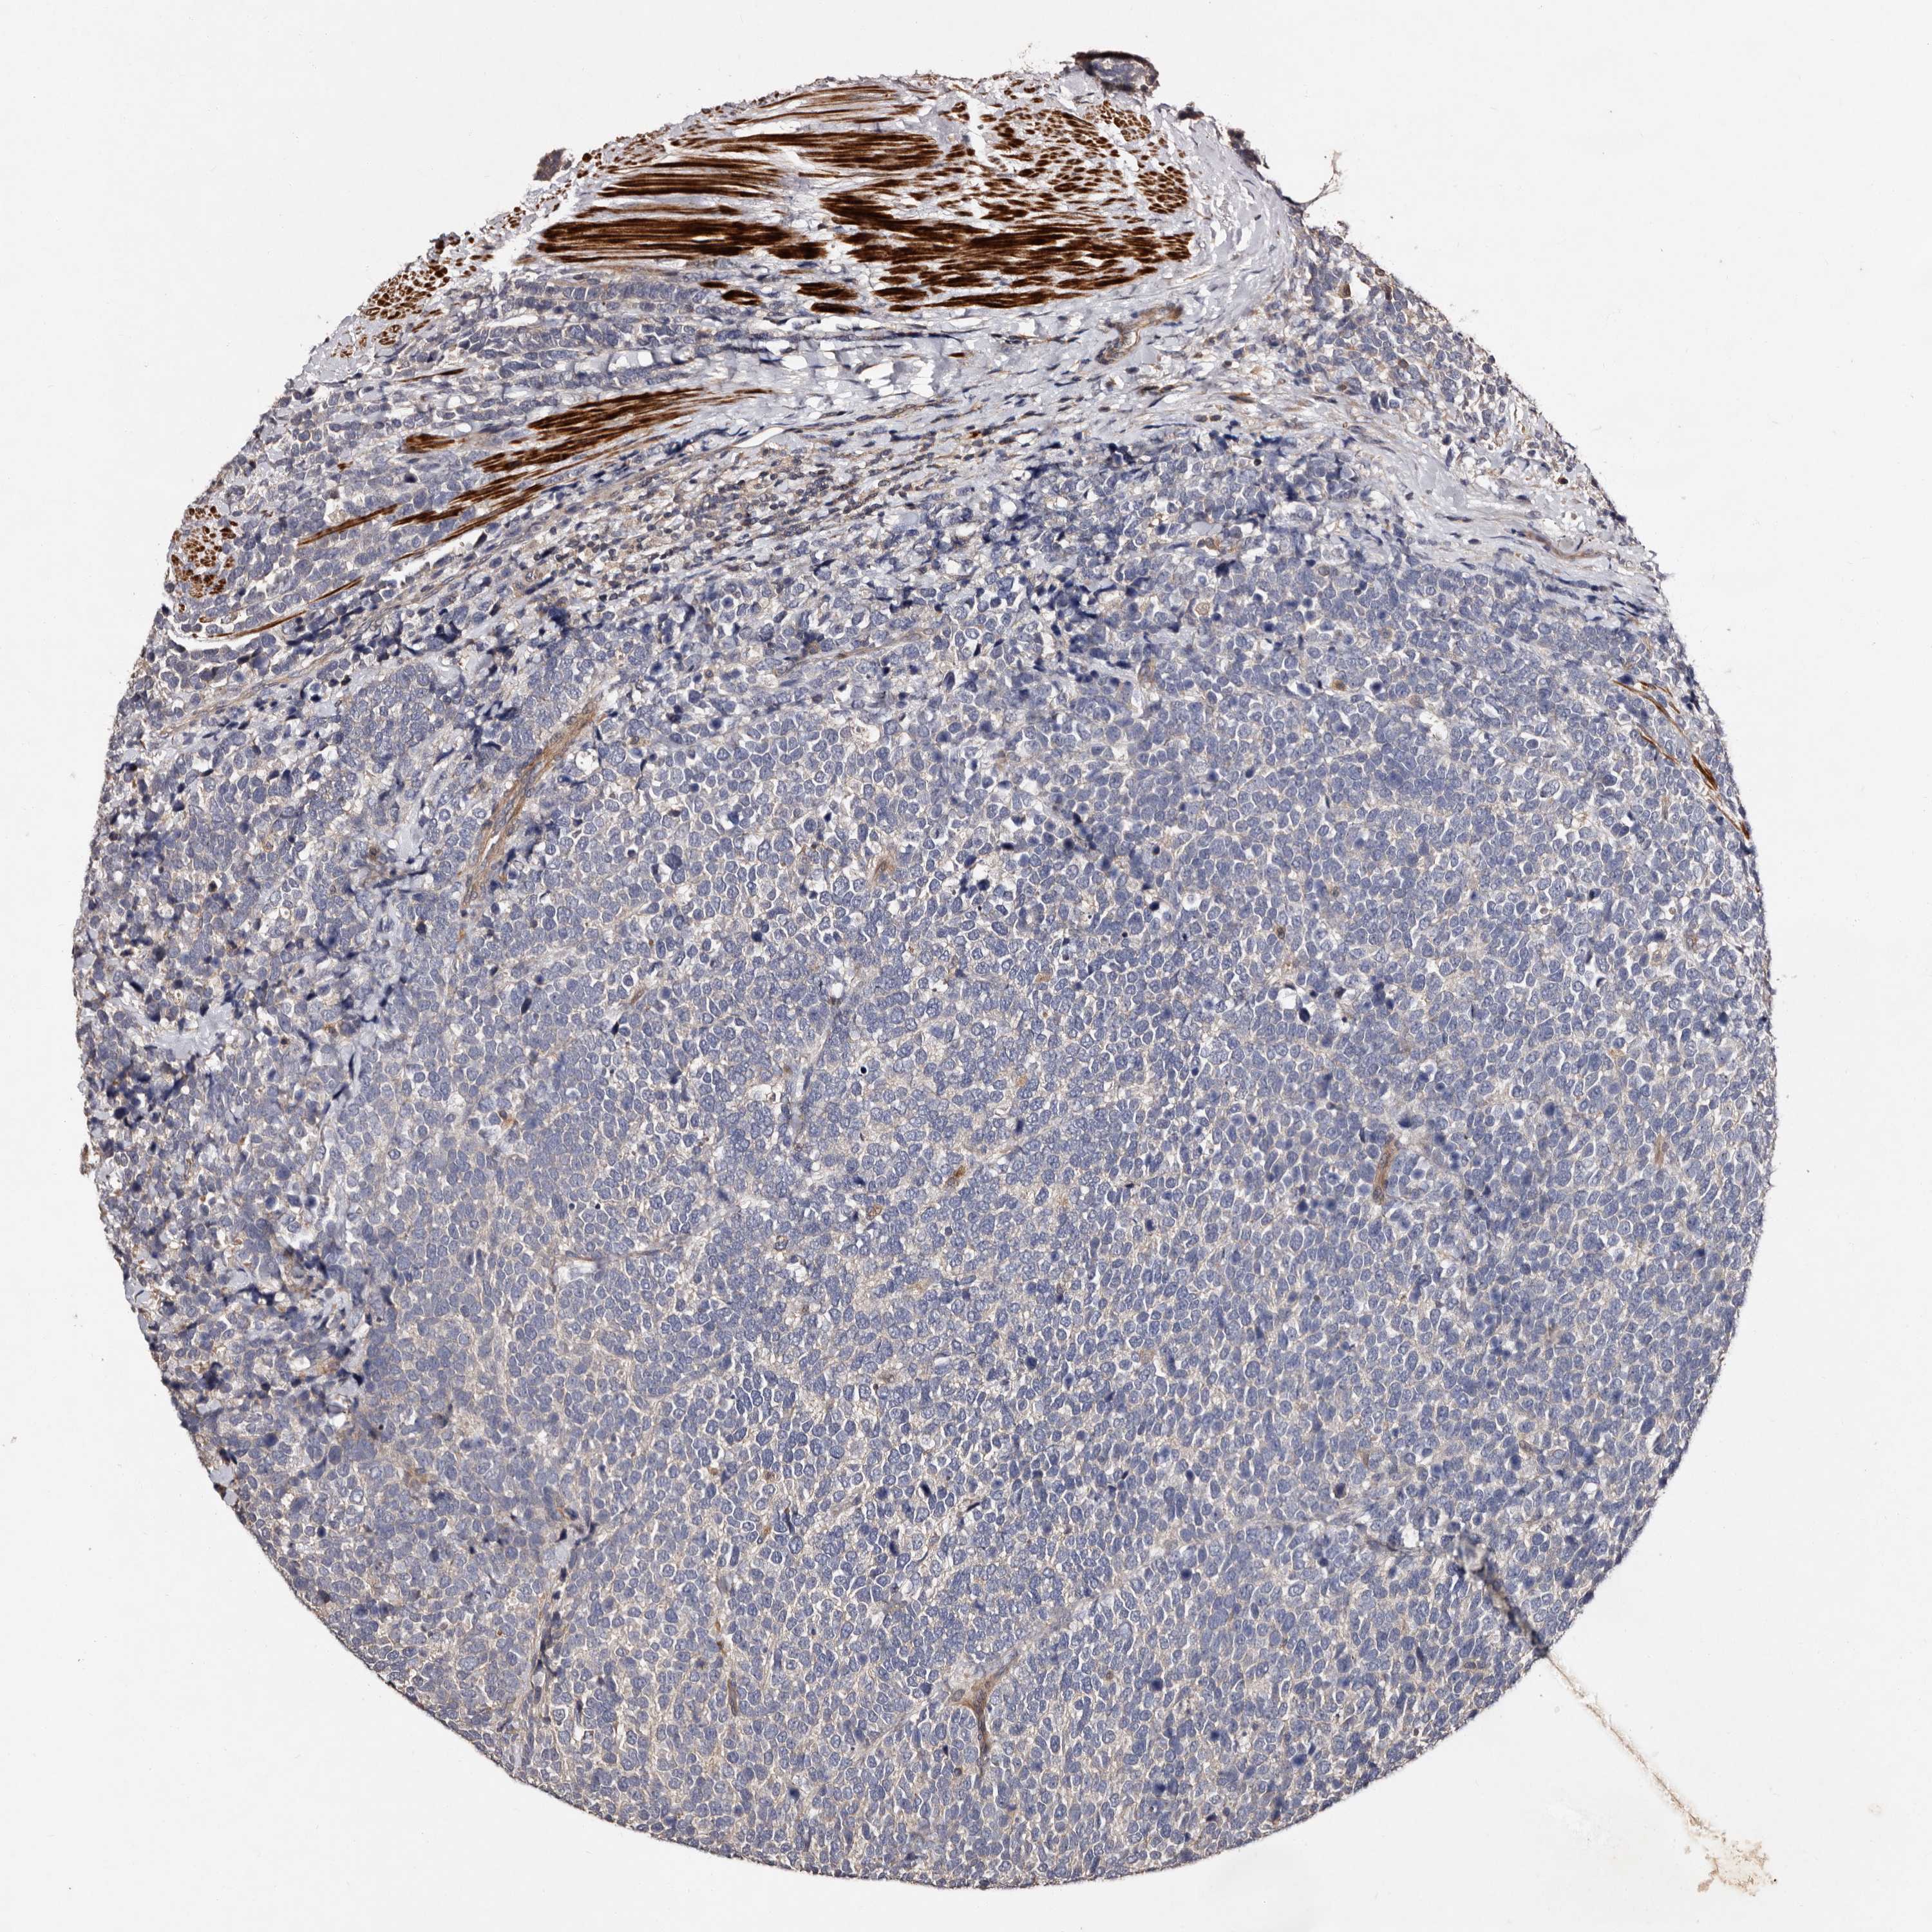

UROTHELIAL CANCER - Protein expressioni

A mouse-over function shows sample information and annotation data. Click on an image to view it in a full screen mode. Samples can be filtered based on level of antibody staining by selecting one or several of the following categories: high, medium, low and not detected. The assay and annotation is described here.

Antibody stainingi

Antibody staining in the annotated cell types in the current human tissue is reported as not detected, low, medium, or high, based on conventional immunohistochemistry profiling in selected tissues. This score is based on the combination of the staining intensity and fraction of stained cells.

Each image is clickable and will lead to virtual microscopy that enables deeper exploration of all samples and also displays staining intensity scores, fraction scores and subcellular localization as well as patient and tissue information for each sample.

Antibody HPA029529

Staining

High

Medium

Low

Not detected

Intensity

Strong

Moderate

Weak

Negative

Quantity

>75%

75%-25%

<25%

None

Location

Nuclear

Cytoplasmic/membranous

Cytoplasmic/membranous,nuclear

Urothelial carcinoma, Low grade

Urothelial carcinoma, High grade